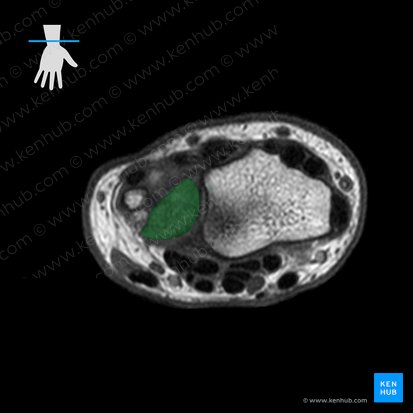

The distal radioulnar joint is the articulation between the crescent-shaped convex distal head of ulna and the concave ulnar notch of radius. Both surfaces are lined by the hyaline cartilage.

The joint contains a triangular fibrocartilaginous articular disc. The apex of the disc is attached to the lateral surface of the styloid process of ulna, while the base is anchored to the inferior margin of the ulnar notch of radius.

Besides taking part in the distal radioulnar joint, the disc participates in the radiocarpal joint with its inferior surface. The disc is thinner centrally than peripherally, meaning that a potential perforation of its central part would open the communication between the distal radioulnar and radiocarpal joints.

Triangular fibrocartilage complex (TFCC)

The triangular fibrocartilage complex (TFCC) is a biconcave ligamentous complex that stabilizes and cushions the joints of the wrist region; distal radioulnar, ulnocarpal and radiocarpal joints. It consists of the articular disc of the distal radioulnar joint, ulnar collateral ligament, dorsal and palmar radioulnar ligaments, the base of the extensor carpi ulnaris sheath, and the ulnolunate and ulnotriquetral ligaments.

The core of the TFCC is the articular disc of the distal radioulnar joint. The dorsal and palmar parts of the TFCC are thickened and known as the dorsal and palmar radioulnar ligaments, respectively. Each of these ligaments consists of the superficial and deep components which differ by their ulnar attachments. The superficial components insert onto the styloid process of ulna, while the deep ones insert slightly more laterally. The ulnar collateral, ulnolunate and ulnotriquetral ligaments join the TFCC on its ulnar attachment. The dorsal margin of the TFCC is fused with the floor of the base of the extensor carpi ulnaris sheath.